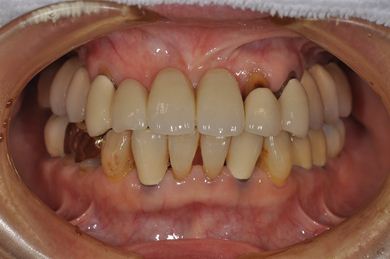

インプラントの症例写真 IMPLANT

| 治療内容 | インプラント8本(抜歯即日スピードインプラント、サイナスリフト)、ハイブリッドセラミック8本 | ||||||||||||||||||||||||||||||||

| 総治療費 | 3,495,050円 | ||||||||||||||||||||||||||||||||

| 治療期間 | 1年0ヶ月 |